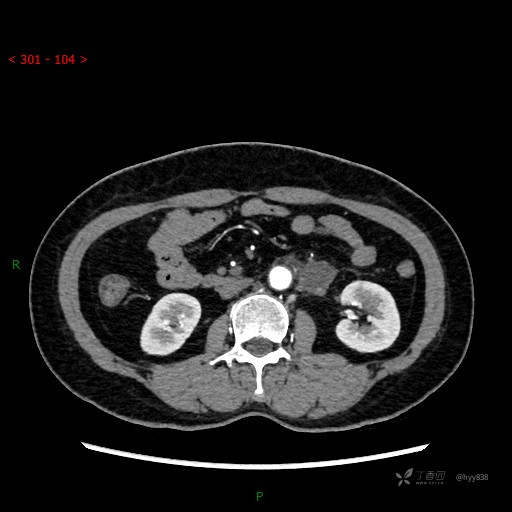

静脉期

CT平扫是外院的,因图像质量原因,不方便上传!